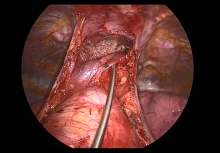

Subxiphoid Uniportal Nonintubated Thymectomy [1]

The authors present a thymectomy that was performed for a 49-year-old woman with a history of breast carcinoma who had a positron emission tomography–positive lesion at the level of the anterior mediastinum.

Her care was discussed at a multidisciplinary meeting and, although there was a suspicion of a malignant thymoma, the radiologist did not consider a computed tomography-guided biopsy to be a feasible option due to the position of the lesion. The patient was then referred for surgical excision.

Subxiphoid VATS has been developed as an alternative surgical approach that provides excellent visualization of both pleural cavities, including the phrenic nerves. Also, the subxiphoid approach has the advantage of avoiding an intercostal incision and intercostal manipulation, reducing pain and thus allowing early aggressive mobilization.